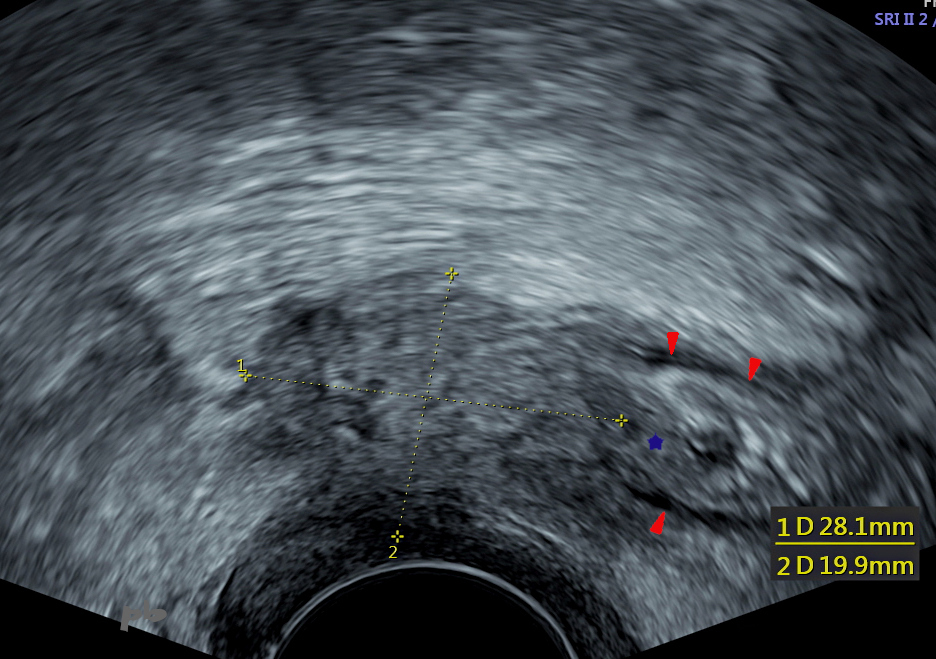

16 – Endométriose postérieure – Echographie

Nodule endométriosique hypoéchogène (croix).

Une portion de ce nodule (★) infiltre la paroi sigmoïdienne. La musculeuse est totalement effacée à ce niveau. Elle reste visible ailleurs (►).